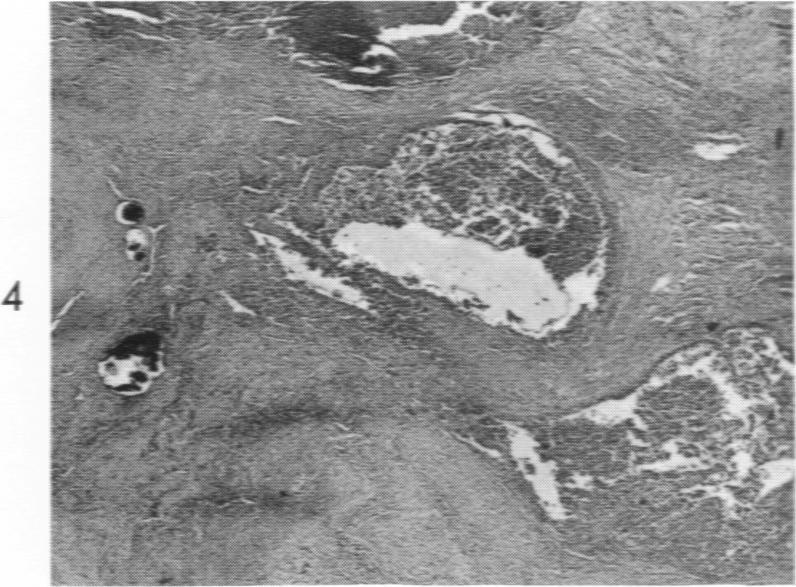

Brucellosis and heart disease. II. Fatal brucellosis: a review of the literature and report of new cases.

Am J Pathol. 1960 Jun;36(6):673-97.